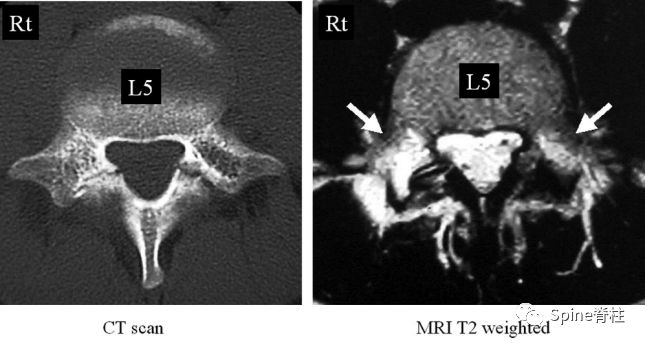

有研究发现磁共振上椎弓根出现T2高信号改变是青少年和儿童峡部裂的早期诊断征象。同时,存在椎弓根高信号改变也是保守治疗后能达到骨性愈合的良好预测指标(也就是说存在T2椎弓根右高信号改变的峡部裂患者,其峡部裂经保守治疗愈合的可能性大)

右上图为椎弓根高信号改变(+),右下图为(-)

左侧为椎弓根水肿阳性,右侧为椎弓根水肿阴性,有研究发现峡部裂伴随着椎弓根水肿,支具固定愈合率更高

Sairyo教授研究发现磁共振上椎弓根出现T2高信号改变是青少年和儿童峡部裂的早期诊断征象。同时,存在椎弓根高信号改变也是保守治疗后能达到骨性愈合的良好预测指标(也就是说存在T2椎弓根右高信号改变的峡部裂患者,其峡部裂经保守治疗愈合的可能性大)。

图:右上图为椎弓根高信号改变(+),右下图为(-)

右图提示椎弓根高信号改变(箭头)

右图提示双侧椎弓根高信号改变(箭头)

右图:右侧椎弓根高信号改变明显,左侧椎弓根轻微高信号

因此,Sairyo教授也提出,对于青少年腰痛患者行MRI检查时,在传统椎间盘层面的基础上(A-C线),多加一个经椎弓根层面(D线)。因为,A-C线椎间盘层面可很好看出青少年腰椎间盘突出和腰椎椎体后缘离断症,而D线经椎弓根层面可以早期诊断出腰椎峡部裂和腰椎椎弓根损伤。